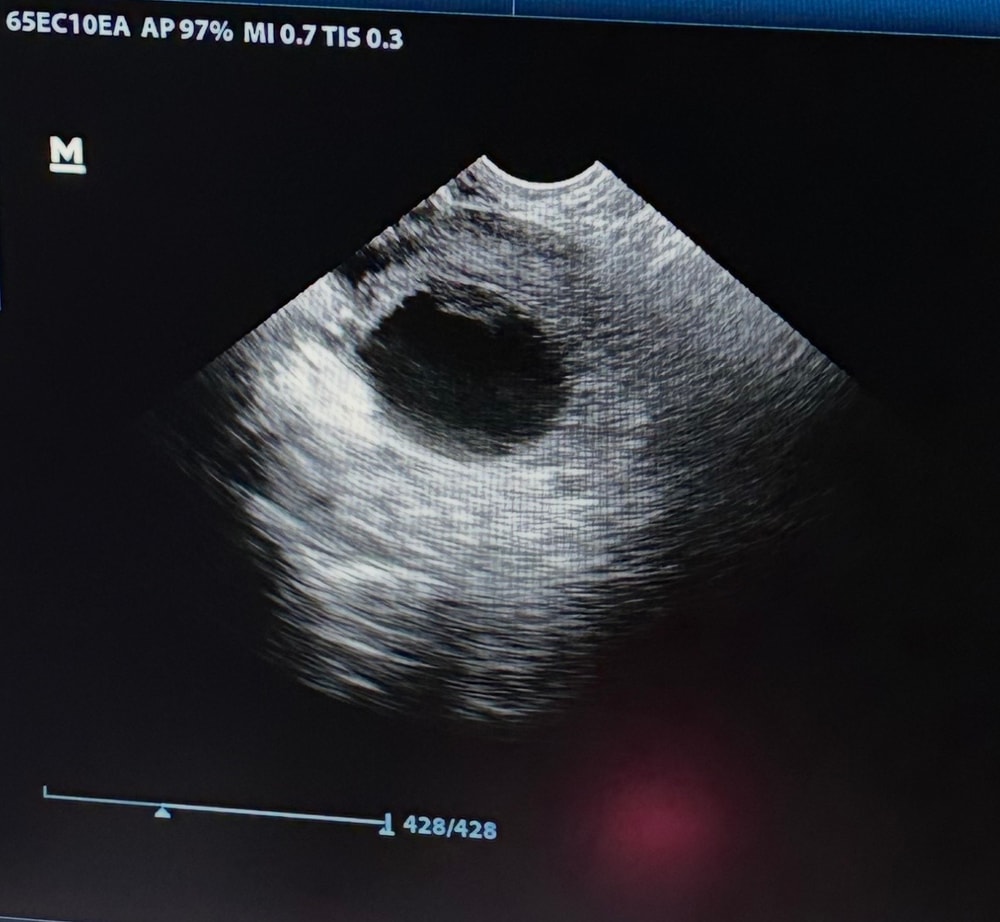

Врач женщина в возрасте. Меня врач зачем-то сразу на узи отвела, ну вот сделали узи. 5 недель. Говорит плодное яйцо есть, нет не жм ни эмбриона. Пя выросло, а в нем ничего😳Я сразу в слезы, не понимаю что это значит. Врач давить начала говорит «куда вы молодежь торопитесь». Со мной муж был его даже не пустили, ладно бог с ним. Врач сказала ну дай бог приходи в 20~ числах декабря может что-то появится. Как так вообще можно сказать??боже….Потащила меня по всем мазкам, ужасно больно делала, было сильно не приятно от всего происходящего. Вылетаю из клиники сразу к мужу и плачу, успокоил меня еле-еле.